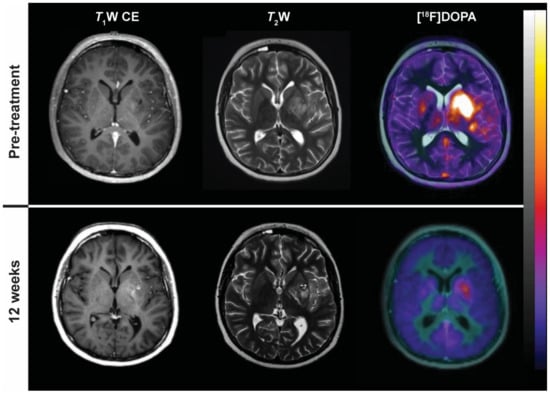

- Cicone, F.; Minniti, G.; Romano, A.; Papa, A.; Scaringi, C.; Tavanti, F.; Bozzao, A.; Maurizi Enrici, R.; Scopinaro, F. Accuracy of F-DOPA PET and perfusion-MRI for differentiating radionecrotic from progressive brain metastases after radiosurgery. Eur. J. Nucl. Med. Mol. Imaging 2015, 42, 103–111. [Google Scholar] [CrossRef] [PubMed]